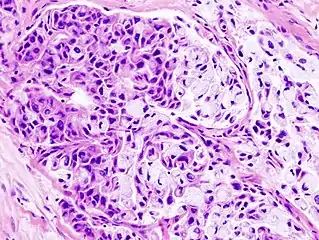

Micrograph of a mucoepidermoid carcinoma. FNA specimen. Pap stain.

In terms of diagnosis we find that histological staining, radiological imaging and molecular diagnostic features all play a role in the evaluation[1] This tumor is not encapsulated and is characterized by squamous cells, mucus-secreting cells, and intermediate cells.[7]